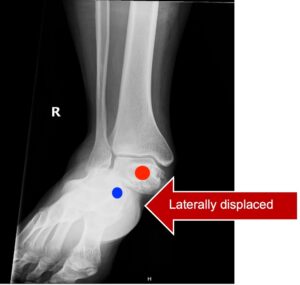

Subtalar Dislocation. Subtalar dislocation, AP annotated. JETem 2024

Subtalar Dislocation. Subtalar dislocation AP annotated. JETem 2024